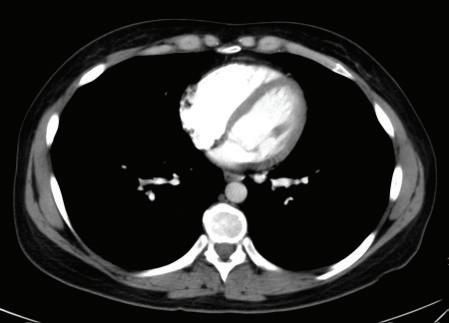

FIGURE 1-20 Three axial chest CT images using different window settings. The top image was made using a soft tissue window. In this image, the different soft tissue densities (note: muscles and intermuscular fat planes) and the bright contrast enhancement of blood in the heart are very conspicuous. The middle image was made using a lung window setting, in which lung markings, mainly pulmonary veins, are visible. The lower image was made using a bone window setting. With these window and level settings, you can see the distinction between marrow and cortical bone in the ribs.